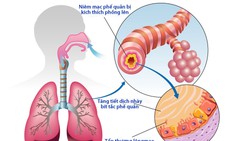

Lương y Hoàng Duy Tân, nguyên phó chủ tịch Hội Đông y Đồng Nai, cho biết viêm phế quản là tình trạng viêm hoặc tắc nghẽn trong các ống phế quản. Các ống phế quản kết nối cổ họng, khí quản đến phổi, phế nang.

Phế nang là túi khí trong phổi, nơi không khí được trao đổi giữa cơ thể và máu, phổi, môi trường. Oxy và các loại khí khác được hít vào và carbon được thở ra. Chất nhầy gây kích ứng và nhiễm trùng phế quản.

Viêm phế quản thường là kết quả sau khi bị nhiễm vi rút, vi rút gây cảm lạnh thường gây viêm phế quản cấp tính. Ngoài ra, viêm phế quản còn được hình thành và phát triển do nhiễm trùng từ việc hít phải khói thuốc lá, và thậm chí cả từ việc tiếp xúc với chất kích ứng trong gia đình và các chất gây ô nhiễm đường phố.

Viêm phế quản có 2 loại là viêm phế quản cấp và viêm phế quản mạn. Viêm phế quản cấp thường xảy ra ở trẻ nhỏ, người lớn tuổi, nhất là về mùa lạnh hoặc khi thay đổi thời tiết.

Viêm phế quản mạn thường do phế quản viêm cấp điều trị không hết hoặc dây dưa lâu ngày chuyển sang thành phế quản viêm mạn. Tuổi từ 50 trở lên dễ bị bệnh. Tỉ lệ mắc bệnh từ 14,2 - 18%. Bệnh kéo dài lâu ngày không điều trị đúng hoặc không khỏi có thể phát triển thành chứng phế khí thủng, tâm phế mạn. Nếu nặng lên sẽ thành chứng suy tim, suy hô hấp.